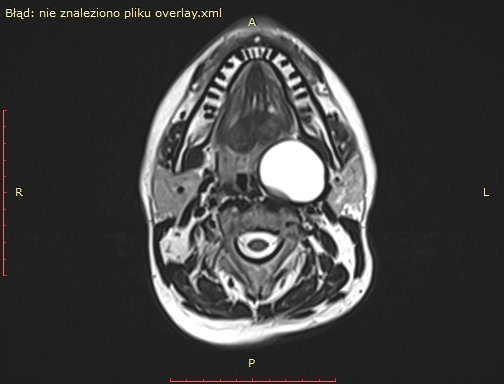

Wielki sukces lekarzy z Oddziału Chirurgii Głowi i Szyi i Chirurgii Robotycznej Szpitala Morskiego im. PCK w Gdyni! Przeprowadzono tam z sukcesem operację usunięcia guza przestrzeni przygardłowej u 48-letniego pacjenta. Zabieg wykonano z wykorzystaniem nowoczesnej technologii chirurgii robotycznej. Pacjent czuje się świetnie! Ta historia zaczęła się bardzo źle. Badanie rezonansu magnetycznego wykazało u 48-letniego pacjenta gdyńskiego szpitala obecność dużej zmiany torbielowatej w przestrzeni przygardłowej po stronie lewej o wymiarach 54x42x38 mm. Zmiana miała postać torbieli zawierającej jednolity płyn, z pogrubiałą, postrzępioną wewnętrzną ścianą i gładką powierzchnią zewnętrzną. Torbiel powodowała przemieszczenie i ucisk okolicznych struktur. Biopsja aspiracyjna cienkoigłowa sugerowała torbiel boczną szyi.Gdyńscy lekarze zdecydowanili się na zastosowanie nowoczesnej technologii chirurgii rozbottycznej. Zabieg przeprowadzono drogą przezustną – po nacięciu przedniego łuku podniebiennego po stronie lewej, uwidoczniono torbiel, którą następnie precyzyjnie oddzielono od otaczających tkanek i usunięto w całości. Ranę w jamie ustnej zamknięto szwami. Operację przeprowadził dr n.med. Dariusz Nałęcz wraz z zespołem lekarsko-pielęgniarskim. Pacjent został wypisany do domu już następnego dnia po zabiegu w dobrym stanie ogólnym i miejscowym, nie zgłaszając istotnych dolegliwości. Samodzielnie przyjmował pokarmy stałe. – mówi dr n. med. Dariusz Nałęcz. - W tym tygodniu pacjent ponownie odwiedził Oddział Chirurgii Głowi i Szyi i Chirurgii Robotycznej Szpitala Morskiego im. PCK w Gdyni, gdzie kontrolne badania pooperacyjne potwierdziły prawidłowy przebieg gojenia. Badanie histopatologiczne potwierdziło, że usunięta zmiana była gruczolakiem podstawnokomórkowym rosnącym w formie torbieli, bez naciekania ściany i całkowicie usuniętym w granicach tkanek zdrowych. Zabieg jest przykładem skutecznego wykorzystania technologii chirurgii robotycznej w leczeniu skomplikowanych przypadków w trudno dostępnych lokalizacjach anatomicznych, zapewniając jednocześnie szybki powrót pacjenta do zdrowia i minimalizując ryzyko powikłań – dodaje dr n.med. Sławomir Piotrowski, ordynator Oddziału Chirurgii Głowi i Szyi i Chirurgii Robotycznej Szpitala Morskiego im. PCK w Gdyni. Gratulujemy lekarzom, a pacjentowi życzymy dużo zdrowia! Galeria zdjęć Pobierz galerię Przed operacją (fot. Szpitale Pomorskie) Pobierz zdjęcie Przed operacją (fot. Szpitale Pomorskie) Pobierz zdjęcie Przed operacją (fot. Szpitale Pomorskie) Pobierz zdjęcie Po operacji (fot. Szpitale Pomorskie) Pobierz zdjęcie Warunki pobierania Wszelkie prawa do zdjęć lub grafik prezentowanych w ramach portalu, należą do Prowadzącego portal lub do podmiotów z nim współpracujących i podlegają ochronie prawnej. Prowadzący portal zezwala na kopiowanie i przedstawianie utworów jedynie w celach niekomercyjnych oraz pod warunkiem zachowania go w oryginalnej postaci i zachowaniem kontekstu tematu, do którego zostało wykorzystaneprzez redakcję gdynia.pl. Opublikowane materiały powinny zawsze zawierać źródło, czyli adres strony www.gdynia.pl. Na publikowanie utworów w innych celach wymagana jest zgoda właściciela strony czyli Prowadzącego portal. Opublikowano: 04.06.2025 12:07 Autor: Aneta Marczak (aneta.marczak@gdynia.pl) Zmodyfikowano: 09.06.2025 13:16 Zmodyfikował: Małgorzata Omachel - Kwidzińska